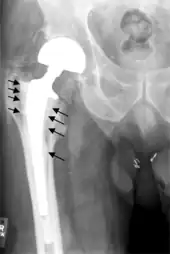

On radiography, it is normal to see thin radiolucent areas of less than 2 mm around hip prosthesis components, or between a cement mantle and bone. These may indicate loosening of the prosthesis if they are new or changing, while areas greater than 2 mm may be harmless if they are stable.[29] The most important prognostic factors of cemented cups are absence of radiolucent lines in DeLee and Charnley zone I, as well as adequate cement mantle thickness.[30] In the first year after insertion of uncemented femoral stems, it is normal to have mild subsidence (less than 10 mm).[29] The direct anterior approach has been shown to itself be a risk factor for early femoral component loosening.[31][32][33]

Hemiarthroplasty

Hemiarthroplasty is a surgical procedure that replaces one half of the joint with an artificial surface and leaves the other part unchanged. This class of procedure is most commonly performed on the hip after an intracapsular fracture of the femur neck (hip fracture). The procedure is performed by removing the head of the femur and replacing it with a metal or composite prosthesis. The most commonly used prosthesis designs are the Austin Moore and Thompson prostheses. A composite of metal and HDPE that forms two interphases (bipolar prosthesis) can be used. The monopolar prosthesis has not been shown to offer any advantage over bipolar designs. The procedure is recommended only for elderly/frail patients, due to their lower life expectancy and activity level. This is because over time the prosthesis tends to loosen or to erode the acetabulum.[84] Independently mobile older adults with hip fractures may benefit from a total hip replacement instead of hemiarthroplasty.[85]

Hip prosthesis for hemiarthroplasty. This example is bipolar, meaning that the head has two separate articulations.

X-ray of the hips, with a right-sided hemiarthroplasty